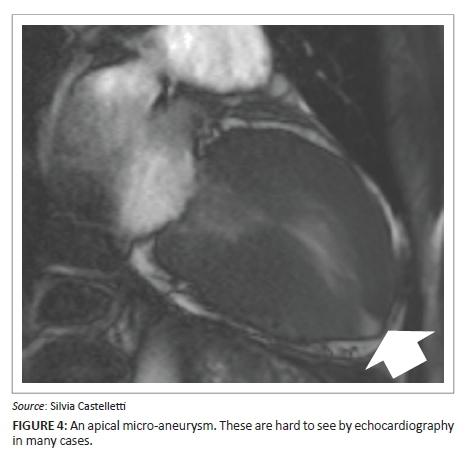

The use of CMR extends the spectrum of detected cardiac changes in HCM. In patients with extensive T-wave inversion but non-diagnostic echo, relative apical hypertrophy may be found that does not meet current diagnostic criteria for HCM and can be demonstrated by CMR. Flett et al.3 described the lack of tapering of the LV wall thickness towards the apex in 22 patients with ECG abnormalities. An apical to basal wall thickness ratio (ABR) >1 is used as a criterion for diagnosis of relative apical hypertrophy (Figure 3). Presence of apical scar, left atrial dilatation and atrial fibrillation was also more common in this group than the general population, and apical micro-aneurysms (Figure 4) also occurred. This appears to be a variant of HCM, although there may be an environmental contribution as the pattern is found sometimes in athletes - raising the suspicion that there are HCM genetic backgrounds where a 'second hit' is required for phenotypic expression.